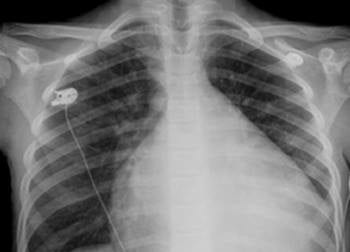

Quando i medici gli hanno fatto la radiografia al tocace hanno impiegato poco tempo per comprendere la causa del malore. Quello che ha lasciato sconvolti i dottori, però, non è stata la scoperta in sé, quanto il fatto che l’oggetto fosse lì da un anno. I medici sono abituati ad avere casi di questo genere ma non si capacitavano del fatto che il ragazzo non si fosse mai rivolto ad un medico prima di quel giorno. Zhang in una serata ad alto tasso alcolico, aveva l’intenzione di stupire i suoi amici con questa bravata. Dopo aver legato il cucchiaio con una sottile cordicella, per poterlo poi tirare fuori, si è reso conto che si era incastrato. Sfortunatamente, preso dal panico aveva tirato troppo forte e la cordicella si era rotta.

Tutti i tentativi di espellere il cucchiaio sono stati vani. I medici, dopo la radiografia, hanno sottoposto il ragazzo a un’endoscopia inserendo dalla bocca un minuscolo tubo di plastica con una telecamera collegata: con un’intervento di circa due ore in anestesia totale sono riusciti alla fine a estrarre il cucchiaio.